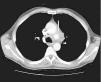

Consultado el caso con el Servicio de Cirugía Cardíaca se decide mantener tratamiento médico y actitud expectante. En ecocardiogramas posteriores mantiene mínimo derrame pericárdico, sin signos de taponamiento y con imágenes de organización en su interior. Presenta buena evolución hemodinámica, respiratoria y general, siendo dado de alta de la UCI a los 5 días de su ingreso. En ecocardiograma transtorácico realizado 10 días después, con el enfermo asintomático, se detecta imagen de probable seudoaneurisma en cayado aórtico, y persistencia de derrame pericárdico. Se practica resonancia magnética nuclear torácica que documenta la presencia de un aneurisma en cayado aórtico, distal a la salida de troncos supraaórticos, probable aneurisma de arteria coronaria derecha y colección intrapericárdica (figs. 3, 4 y 5).

Figura 3. Tomografía computarizada de tórax: imagen de aneurisma en cayado aórtico (flecha).